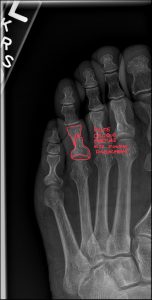

We are committed to enhancing patient care by delivering top-tier medical imaging evaluations and reports consistently. Our team of board-certified radiologists brings specialized expertise in diagnostic imaging, with a particular focus on chiropractic radiology that specializes in spine and musculoskeletal imaging. We strive to provide not just readings, but invaluable consultations, ensuring each patient receives the best that modern radiology has to offer. Our dedication to accuracy, speed, and reliability in off-site image interpretations sets us apart as trusted partners in healthcare.